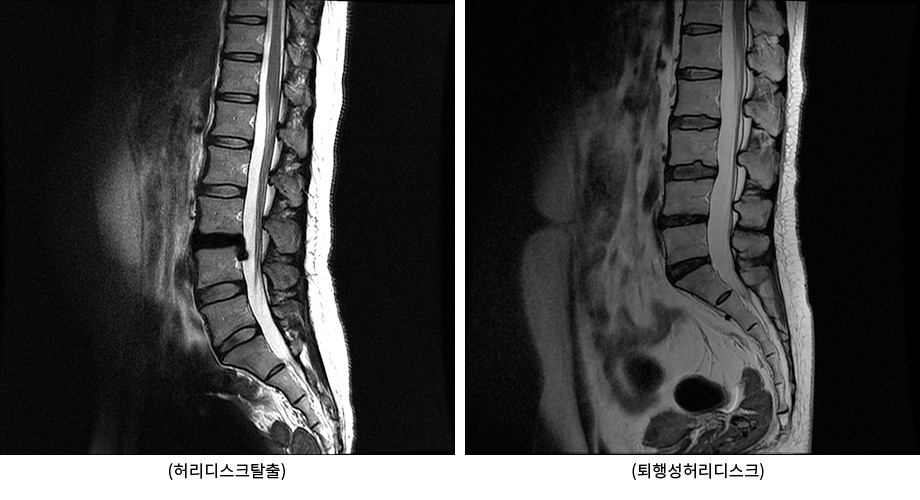

그럼 허리디스크탈출과 퇴행성허리디스크의 차이점은 무엇일까요? 허리디스크탈출은 디스크 외부를 보호하고 있는 섬유륜이 찢어져 수핵이 밖으로 밀려나와 다리로 가는 신경을 건드리면서 염증을 일으키고, 이에 따라 허리 통증과 극심한 다리 통증을 유발하는 급성기 상태를 말합니다. 이에 반해 퇴행성허리디스크는 허리디스크 탈출 후 급성기를 지나 디스크 손상이 복구되면서 어느 정도 안정화된 상태 혹은 허리디스크탈출 없이 나이가 들면서 허리 디스크의 퇴행이 진행된 상태를 의미합니다. 이런 두 질환의 차이로 인해 운동법, 관리법, 치료법도 완전히 달라지게 됩니다. 따라서 허리디스크탈출과 퇴행성허리디스크는 꼭 구별해주어야 합니다.